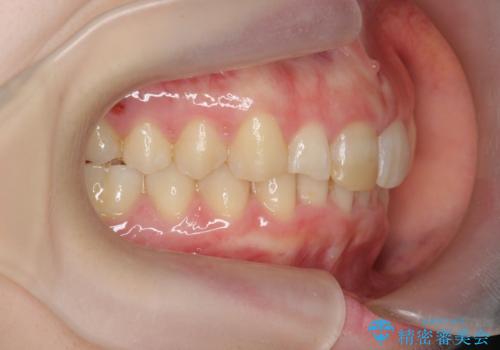

前歯のがたつき 深い噛み合わせを改善したい

- 「前歯のガタつきをきれいにしたい、噛んだ時に下の前歯が見えないことを改善したい」とマウスピース矯正を希望され来院されました。

マウスピースに加え、矯正用マイクロインプラントやゴムを併用し、がたつきや噛み合わせの深さを改善していきます。

ゴムかけやマウスピースの装用時間、しっかりとマウスピースをはめ込むチューウィーをしっかりと使用したことで良好な治療結果を得ることができました。